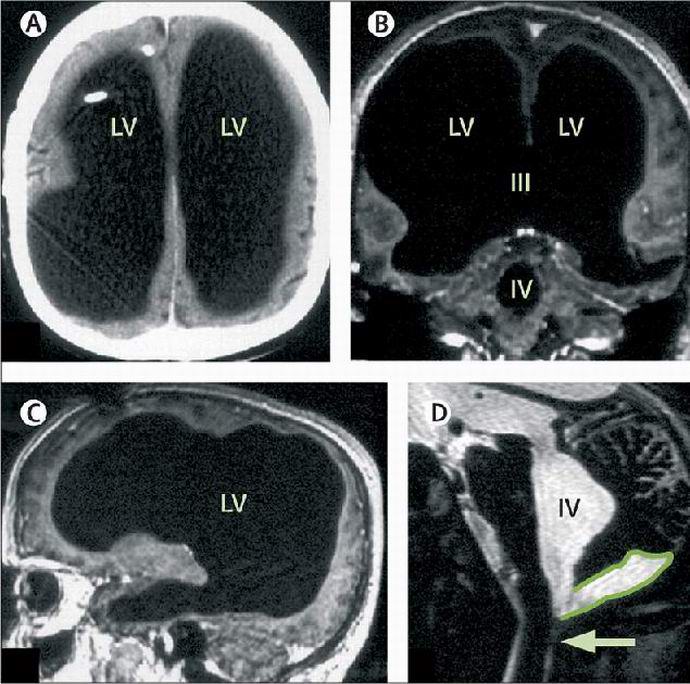

Primer francoskega javnega uslužbenca po imenu Mathieu je prava skrivnost svetovne medicine. Nekaj moških desetletja živel s tako drobnimi možgani, da je leta 2007 ko so zdravniki po naključju odkrili to anomalijo pri njem, so najprej organov v lobanji sploh niso opazili. Neverjetno Francoski zdravniki so odkrivanje odkrili, ko se je Mathieu obrnil pritoževal se je zaradi bolečin v nogah. Standardni pregledi in analize niso dovolili za postavitev diagnoze in nato zdravstveno osebje institucije so se odločile za popolno zdravstveno raziskavo stranka.

Ko so zdravniki dosegli Mathieuvo preiskavo možganov, so se izkazali dobesedno šokiran. Moški možgani so bili tako majhni da na slikah praktično ni bilo opaziti. Po seriji testi, zdravniki so ugotovili, da je možganska tekočina oz. kroži v zdravi osebi v možganih in se izloča v obtočni sistem, napolnil lobanjo bolnika, odhod zelo majhna količina sive snovi. To ga je prizadelo strokovnjaki za iskanje so začeli razumevati naravo pojava in ugotovili, da se je v otroštvu moški zdravil zaradi hidrocefalusa – drugo z besedami so mu iz možganov črpali odvečno tekočino. Za to zdravniki Mathieu je imel shunt in nato odstranil šant. Ampak, kot je vidno, težava po tem ni izginila.

Pol stoletja se je v lobanji nabrala odvečna tekočina Francoz je skrinjo in si napolnil možgane. Neverjetna, a bolečina v nogah postal prvi in doslej edini zaplet, povezan z njegovim bolezen. Znanstveniki so zadnjih osem let natančno preučevali telo. Mathieu. Majhne velikosti njegovih možganov naj bi bile posledica hidrocefalusa, pa vendar, kako je moški mirno živel vsa ta leta je prava skrivnost.